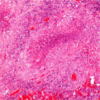

What is shown here?

viral pneumonia

lots of inflammation & lymphocytes in the interstitium

-could also be mycoplasma as that attracts lymphocytes as well